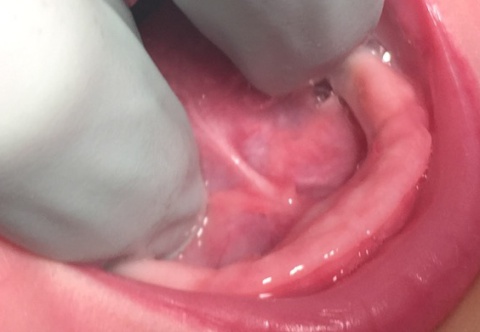

Type 2 Ankyloglossia